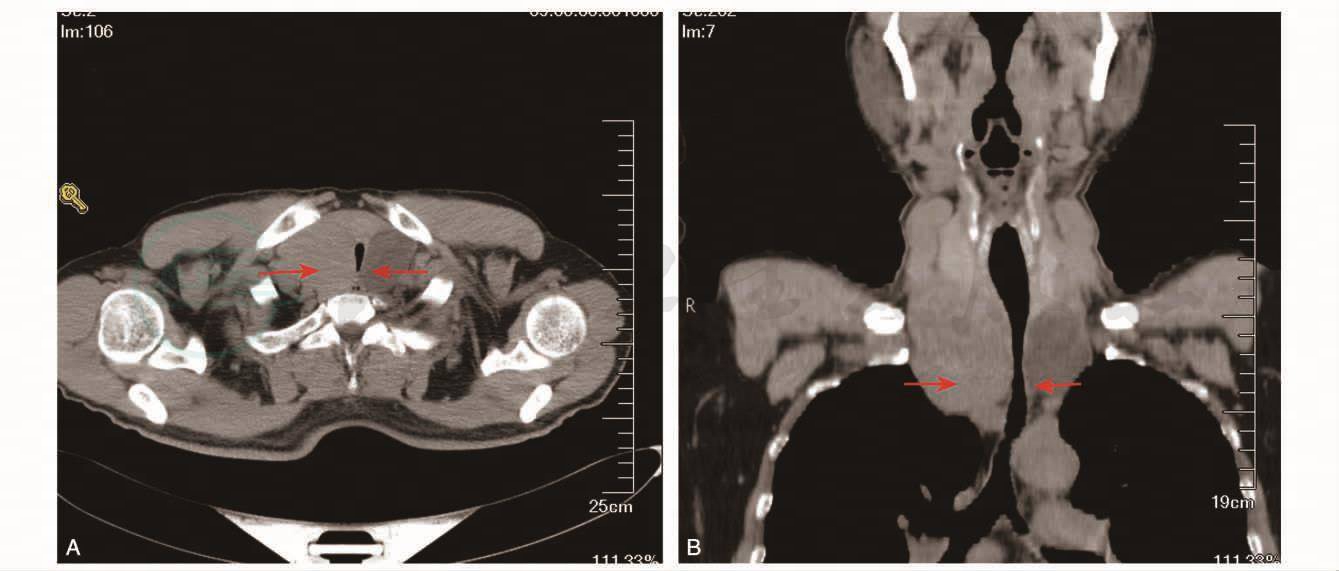

颈胸部CT:双侧甲状腺增大,向下延伸至胸骨后,其内见多发低密度结节,部分有囊性变。气管受压狭窄、左移(图2)。甲状腺彩超:双侧甲状腺增大,见多个低回声结节及囊性肿物。

图2 颈胸部CT示双侧甲状腺增大,向下延伸至胸骨后,其内见多发低密度结节,部分有囊性变。气管受压狭窄、左移(箭头所示)